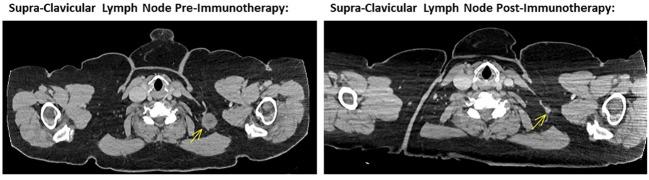

A 66-year-old woman with a background of metastatic, unresectable melanoma with supraclavicular and axillary lymph nodal involvement presented with a headache, photophobia and diplopia 3 weeks after her first cycle of ipilimumab and nivolumab. She was subsequently diagnosed with a left-sided cranial nerve VI palsy and treated with high dose oral steroids and steroid eye drops, with complete resolution of symptoms. She also experienced Grade 3 dermatitis requiring topical steroids, Grade 2 hypothyroidism and vitiligo. She continues to have an excellent clinical and radiological response, despite further immunotherapy being suspended.

一名66岁女性,有转移性、不可切除黑色素瘤病史,伴有锁骨上和腋窝淋巴结受累,在接受第一周期伊匹木单抗和纳武单抗治疗3周后出现头痛、畏光和复视。随后她被诊断为左侧颅神经VI麻痹,并接受了高剂量口服类固醇和类固醇眼药水治疗,症状完全缓解。她还出现了需要局部使用类固醇的3级皮炎、2级甲状腺功能减退和白癜风。尽管暂停了进一步的免疫治疗,但她的临床和影像学反应仍然良好。